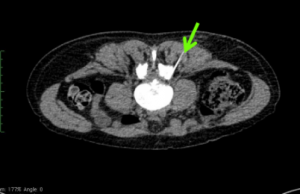

案例:85 歲婆婆,透過CT scan 電腦斷層掃描 的導引下, 進行撰擇性脊椎神經根硬暯外注射,得到即時止郊果.

透過CT X 光機導引下, 進行脊椎神經根注射